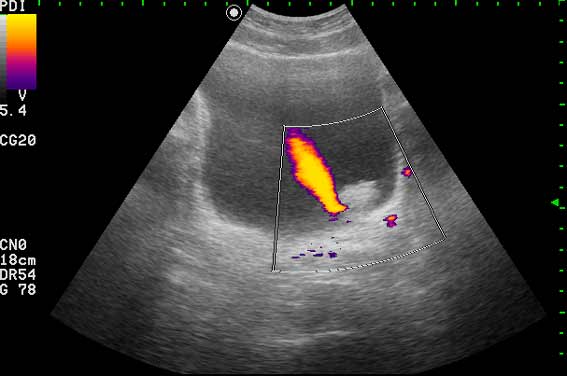

Ну конечно же, на представленных эхограммах - папиллярная опухоль мочевого пузыря.

Писать в заключении, что это полип - нельзя, это случай при котором руководствуются правилом - считаем опухоль злокачественной, пока не доказано обратное. Опухоль расположена над устьем левого мочеточника, нет обструкции устья и терминального отдела мочеточника (доказательство - наличие полноценного выброса мочи из устья) - что, в свою очередь, говорит против интралюминальной уретеральной опухоли.